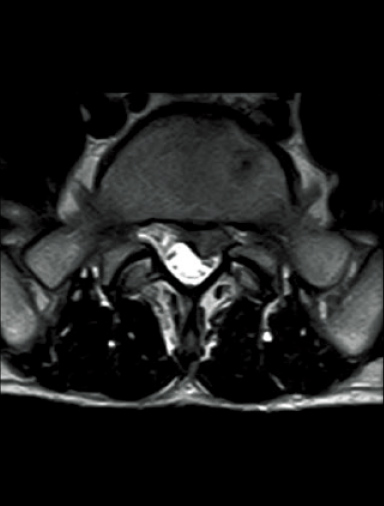

T2WI